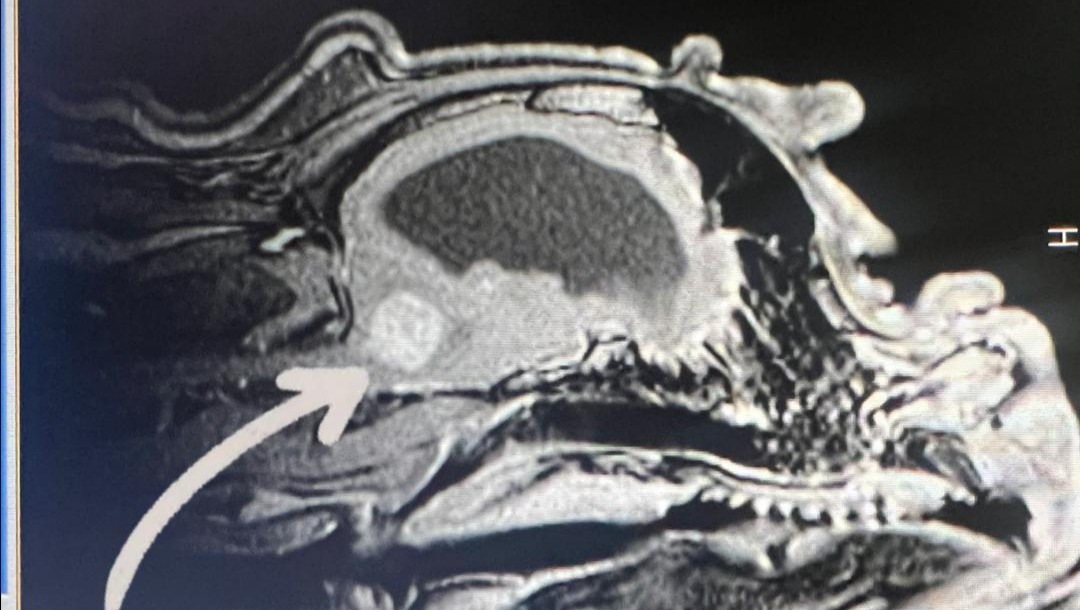

Dejaré anexadas fotos del presupuesto y de la resonancia magnética que le realizaron a Stitch en donde se observa el tumor (que está entre el cerebelo y la columna; una ubicación sumamente complicada de operar) y también se observa su tamaño (es como una pelota de Ping pong, es decir, muy grande). Eso le está causando obstrucción del líquido cefalorraquídeo y crea una hidrocefalia, la cual causa que Stitch no pueda caminar con normalidad, respirar, un síndrome vestibular y otras afecciones que poco a poco le costarán la vida.